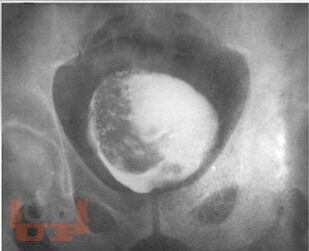

Учебное пособие содержит современную характеристику факторов риска развития рака мочевого пузыря (РМП), что позволит из общей массы амбулаторно-поликлинического приёма более чётко выделять тех пациентов, у которых имеется высокий риск развития онкопатологии. Рассмотрены важные клинические симптомы различных вариантов РМП, методы диагностики, лечения и профилактики, направленные на повышение онкологической настороженности среди врачей и населения. Предложенные авторами алгоритмы обследования больных в амбулаторном звене при первичном обращении пациента подчинены единой концепции и дают возможность индивидуализировать, упорядочить и контролировать работу по своевременной диагностике раковых заболеваний.